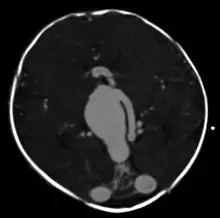

Large arteriovenous malformation of the parietal lobe | |

vein of Galen malformation

A cerebral AVM diagnosis is established by neuroimaging studies after a complete neurological and physical examination.[5][12] Three main techniques are used to visualize the brain and search for an AVM: computed tomography (CT), magnetic resonance imaging (MRI), and cerebral angiography.[12] A CT scan of the head is usually performed first when the subject is symptomatic. It can suggest the approximate site of the bleed.[3] MRI is more sensitive than CT in the diagnosis, and provides better information about the exact location of the malformation.[12] More detailed pictures of the tangle of blood vessels that compose an AVM can be obtained by using radioactive agents injected into the blood stream. If a CT is used in conjunction with an angiogram, this is called a computerized tomography angiogram; while, if MRI is used it is called magnetic resonance angiogram.[3][12] The best images of a cerebral AVM are obtained through cerebral angiography. This procedure involves using a catheter, threaded through an artery up to the head, to deliver a contrast agent into the AVM. As the contrast agent flows through the AVM structure, a sequence of X-ray images are obtained.[12]